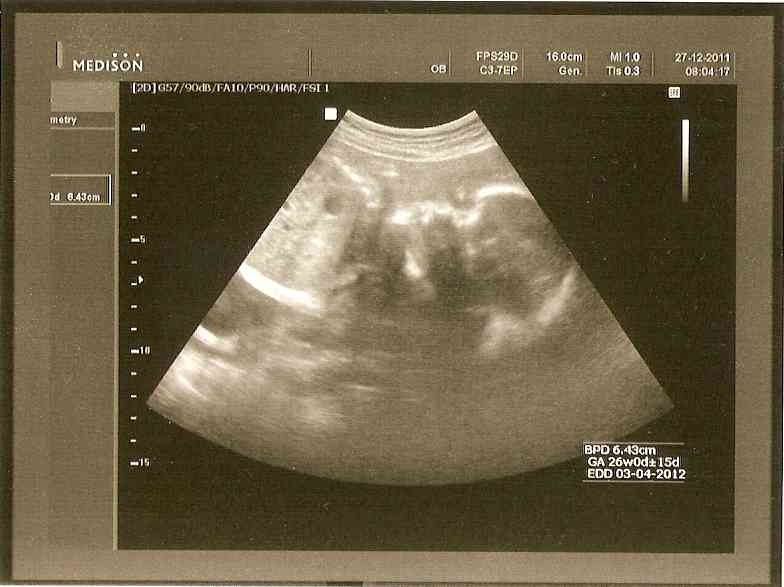

Takže, jako první by se slušelo přidat historicky úplně první fotečky. Tvoje fotečky z doby, kdy jsi byla tzv. "na houbách"

...taky se divíš, jak v tom někteří dokážou rozeznat človíčka? Některé babičky najdou i podobnost a markanty, které se v rodině dědí po generace. Nechám na tobě....poznáš se :D

Omlouvám se a ač jsi mě (věřím že nechtěně) učinila dědečkem - nepoznám tě. Nejsem asi ten správný dědeček, který svoje první vnouče pozná i po tmě. Pro mě je toto foto jen další důkaz mimozemského života na naší planetě. V případě, že se budeš zajímat o datum pořízení těchto dvou foteček z ultrazvuku - klikni na fotku a v rohu je datum.

V té době, kdy byla tato fotka pořízena jsi byla se svými rodiči v bydlišti tvé maminky Hanky. Ten konec světa u Klatov, kousek od hranic z Německem se jmenuje Milence (o další info požádej rodiče).